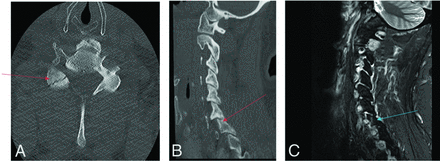

Fracture-positive, radiologist true-positive, CNN false-negative case example. Axial (A) and sagittal (B) cervical spine CT images, and sagittal fat-saturated T2-weighted cervical spine MR image (C) demonstrate a C6–7 fracture-dislocation with cord compression. Red arrows demarcate fracture-dislocation, the blue arrow demarcates prevertebral edema, and the orange arrow demarcates cord compression. This case example illustrates an important drawback of the CNN to overlook areas of gross bony translation, as it was only designed to detect linear bony lucency in patterns consistent with fractures.